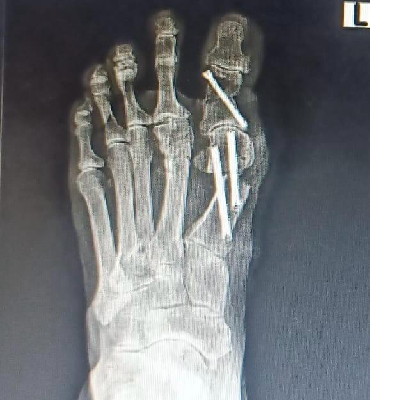

Minimally Invasive Surgery (MIS) :